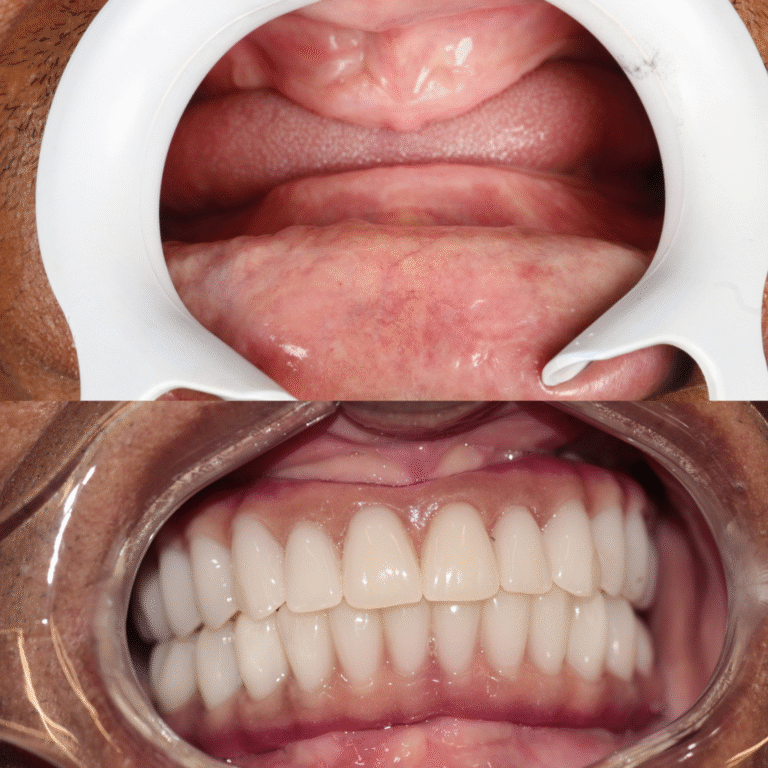

O All-on-Four é um protocolo de implantes dentários que utiliza apenas 4 implantes para fixar uma prótese total, substituindo todos os dentes da arcada.

Diferente de técnicas convencionais, não exige enxertos ósseos na maioria dos casos, tornando o tratamento mais rápido e confortável.

Em muitos casos, é possível instalar dentes fixos no mesmo dia da cirurgia. Isso significa que o paciente recupera a estética do sorriso e a função mastigatória muito mais rápido do que em técnicas convencionais.